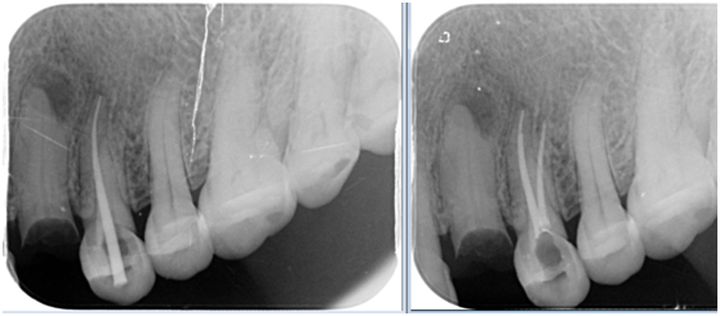

根管治疗遇到髓室底底穿,根管壁侧穿,根管充填欠填、超填,遗漏根管,断针,根管折断……等情况均可能导致根管治疗的失败。

(黄色线为牙根,白色线为根充物)

所有的治疗,都没有百分之一百的成功率,随着牙体牙髓学理论的进步,技术的发展,根管治疗的远期成功率,也只能无限的接近百分之一百。

因此,即便我们在根管治疗时,出现上述情况,也别太过于害怕,请相信你的牙医,他们会尽力避免上述情况的出现,一旦出现上述情况,仍有一定的补救手段可以使用。